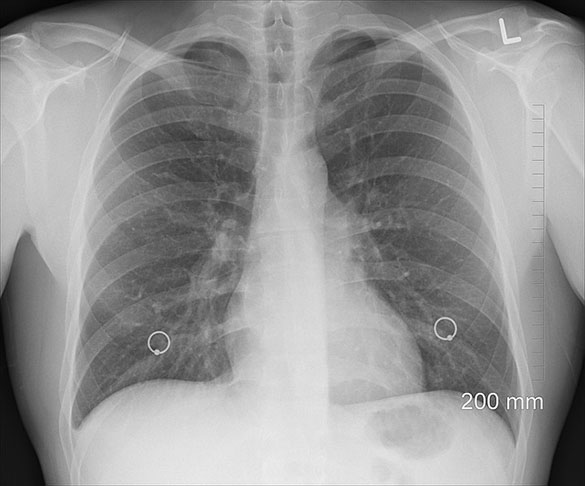

Por isso, no caso de qualquer preocupação com seus pulmões, Dickinson recomenda consultar um médico em busca de um teste de função pulmonar apropriado. Ele envolve respirar em um aparelho chamado espirômetro, que mede o volume e a velocidade da respiração.

O espirômetro irá calcular sua CVF com precisão de grau médico, além do seu volume de expiração forçada (VEF1), que é a quantidade de ar que você consegue exalar em um segundo, após uma respiração profunda.

O aparelho também fornecerá a razão entre o VEF1 e a CVF, o que pode indicar eventuais obstruções do fluxo respiratório. Combinadas, estas medidas fornecem um quadro geral da saúde pulmonar.